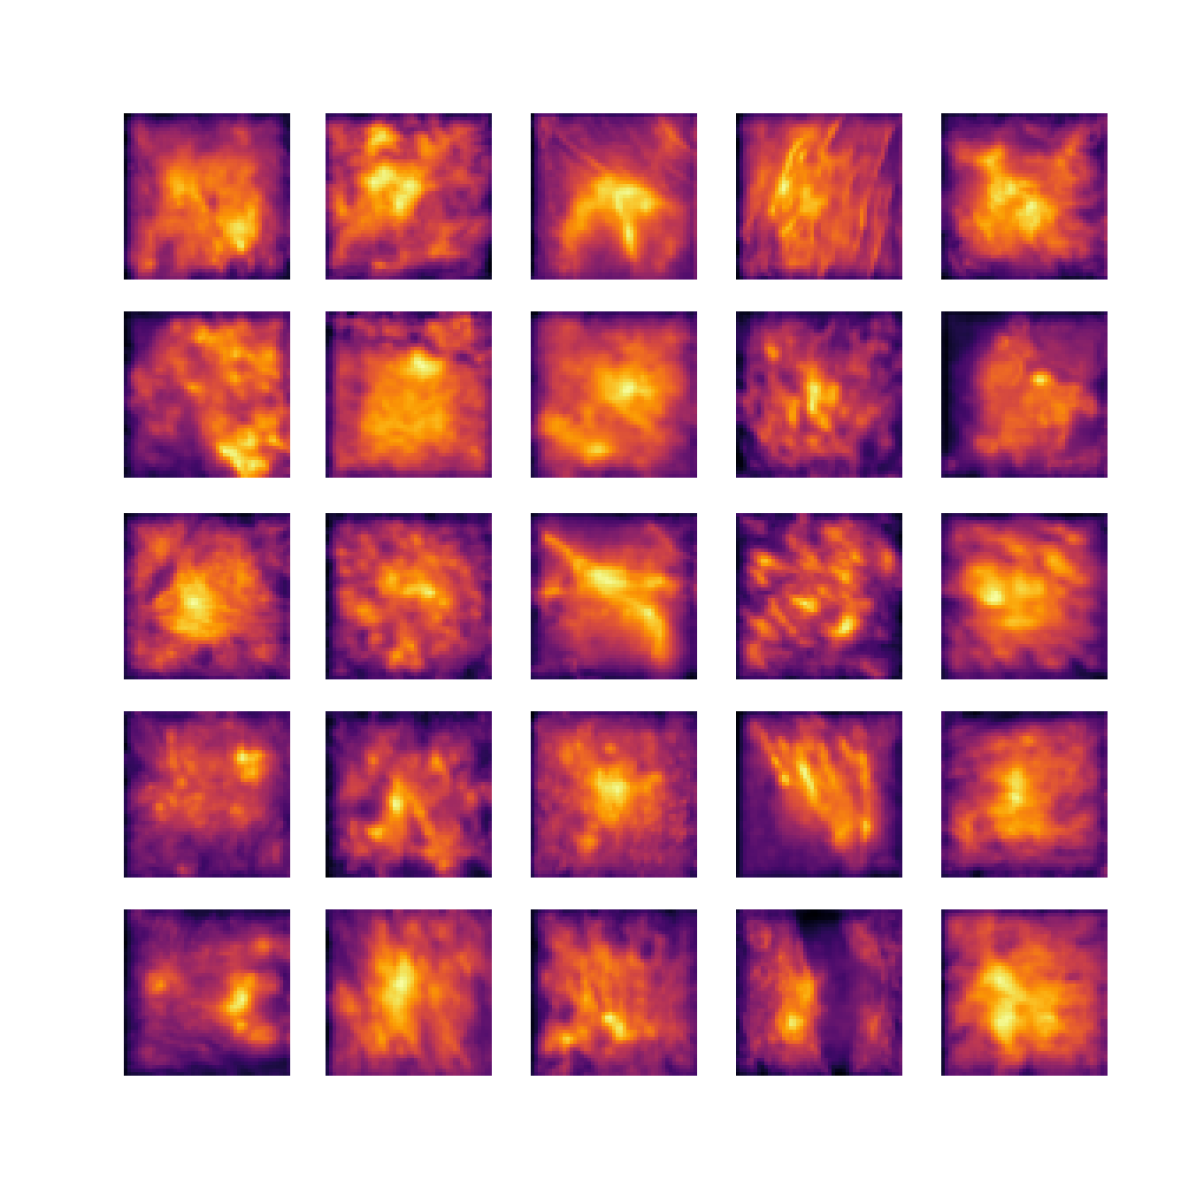

We also analyse the activation maps for each model using GradCAM as described in section S3. This offers more insight into the areas of the image which are contributing most heavily to the models’ representations. In Figure 4(b) we present some representative examples, however, a larger selection which was chosen at random is presented in Figures S10 to S25. The larger selection makes it easier to see the emergent patterns, including that privileged Siamese models tend to mainly identify features which are strongly present in both inputs, while unprivileged Siamese models tend to learn more diffuse features that are not specific to one cell phenotype or image region. TriDeNT ♆ incorporates both sets of features, learning both features specific to the privileged data and more the general features associated with unprivileged Siamese networks.

We can see in Figure 4(b) panel A that for ERG, the privileged Siamese model focuses almost exclusively on any nuclei which could be endothelial cells. As there are very few endothelial cells in the dataset, it could be an effective strategy to identify anything that could potentially be an endothelial cell to minimise the difference between the representations of the H&E model and the IF mask model. In the corresponding unprivileged Siamese image, we see that the model identifies some of these nuclei, albeit less strongly, but also focuses heavily on the other tissue and even the background, while strongly fixating on two spots of debris in the center of the image. This model has less ‘incentive’ to learn the weak features related to endothelial cells as these occur rarely and are not easy to detect, while more generic strong features such as the presence of connective tissue and the prevalence of background are more common and predictable from augmented images. We see that TriDeNT ♆ combines these two feature sets, strongly identifying nuclei while also identifying the connective tissue.

In panel C we see a similar pattern, with the privileged Siamese model fixating solely on the nuclei, while the TriDeNT ♆ model takes a more balanced approach. The unprivileged Siamese model appears to focus on a single cluster of nuclei while neglecting others, and similarly identifies an area of fibroblasts with its distinctive pattern but does not others.

In contrast to panels A and C which represent models with poor privileged Siamese results, panels B and D represent models whose privileged Siamese results were comparable to both TriDeNT ♆ and even the supervised baseline. It is therefore interesting to note that there are far more similarities between the privileged Siamese and TriDeNT ♆ models in both cases. Particularly in panel B, TriDeNT ♆ and the privileged Siamese model return virtually identical heatmaps, with both strongly identifying epithelial nuclei and neglecting the same areas of connective tissue. The unprivileged model in this case appears to focus solely on the centre of the image, giving a significantly different heatmap to the other panels.

Panel D again shows the previous pattern, with the privileged Siamese model identifying the features strongly present in the privileged data – fibroblasts – while neglecting the nuclei present. TriDeNT ♆ also strongly identifies the connective tissue, but, unlike the privileged Siamese model, does not completely neglect the nuclei. The unprivileged Siamese model primarily identifies background, and does not appear to identify the nuclei in this example.